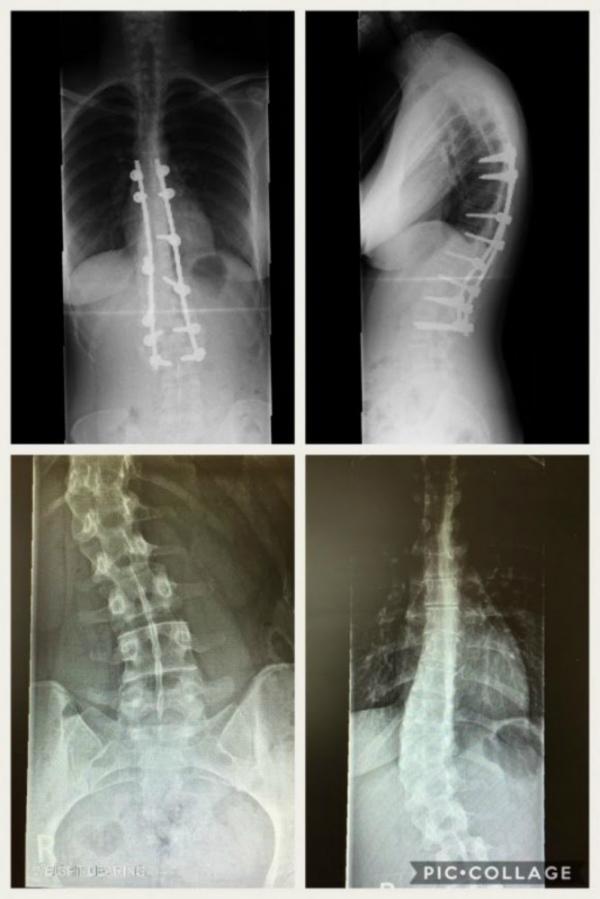

▼ 她也PO出術前術後的X光照片,證實了手術的確十分有效。

這個手術首先會在脊椎骨上鎖上鋼釘、鋼鉤,把上下的骨頭用外力拉直、轉正,絕對是個不小的手術,若側彎比較嚴重,還要從身體正麵對韌帶、椎間盤、軟骨打上拉力支架。